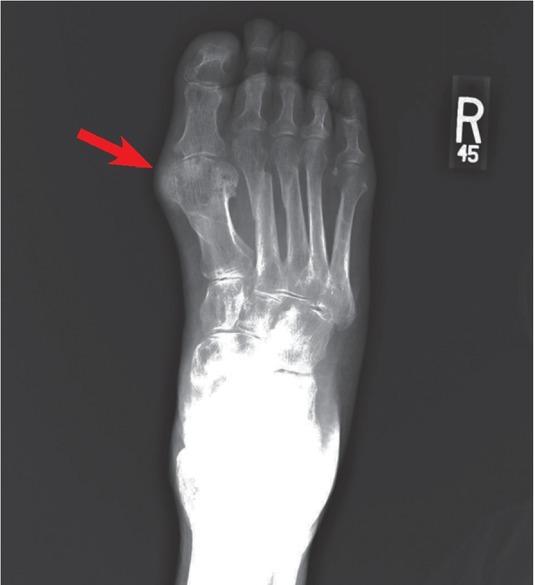

异位骨化:影像学与病理学综述

Heterotopic ossification: radiological and pathological review.

Background Heterotopic Ossification (HO) is a common condition referring to ectopic bone formation in soft tissues. It has two major etiologies, acquired (more common) and genetic. The acquired form is closely related to tissue trauma. The exact pathogenesis of this disease remains unclear; however, there is ongoing research in prophylactic and therapeutic treatments that is promising. Conclusions Due to HO potential to cause disability, it is so important to differentiate it from other causes in order to establish the best possible management.

摘要

背景 异位骨化(HO)是一种常见病症,指的是软组织中异位骨的形成。它有两种主要病因,后天性(更常见)和遗传性。后天性形式与组织创伤密切相关。该疾病的确切发病机制仍不清楚;然而,目前在预防性和治疗性治疗方面的研究很有前景。结论 由于HO有导致残疾的可能性,为了制定最佳治疗方案,将其与其他病因区分开来非常重要。